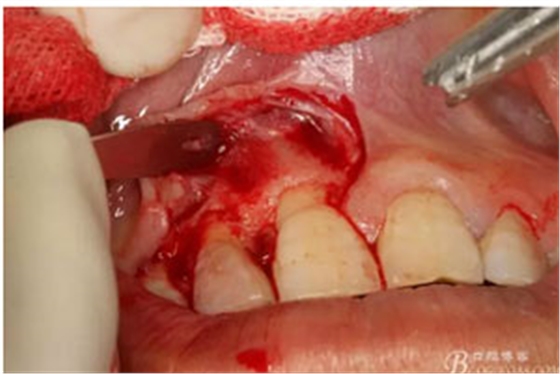

圖8.從垂直切口和水平切口的連接處翻瓣。發(fā)現(xiàn)11和12之間的骨壁有缺損。

圖9.翻開角形瓣后,有骨壁缺損,囊壁有穿孔,這就是溢膿的竇道出口。